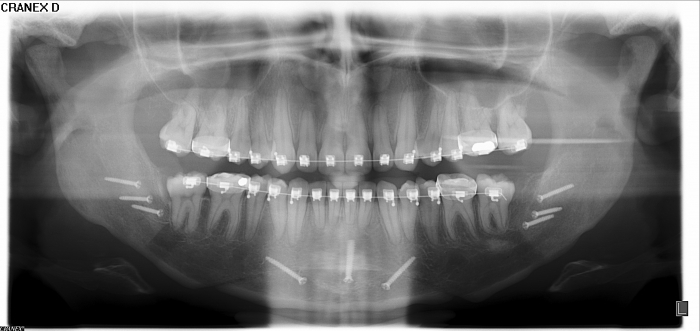

Rx Panorâmico após cirurgia realizada em 2015 - Clínica Cliniface

Rx Panorâmico após cirurgia realizada em 2015